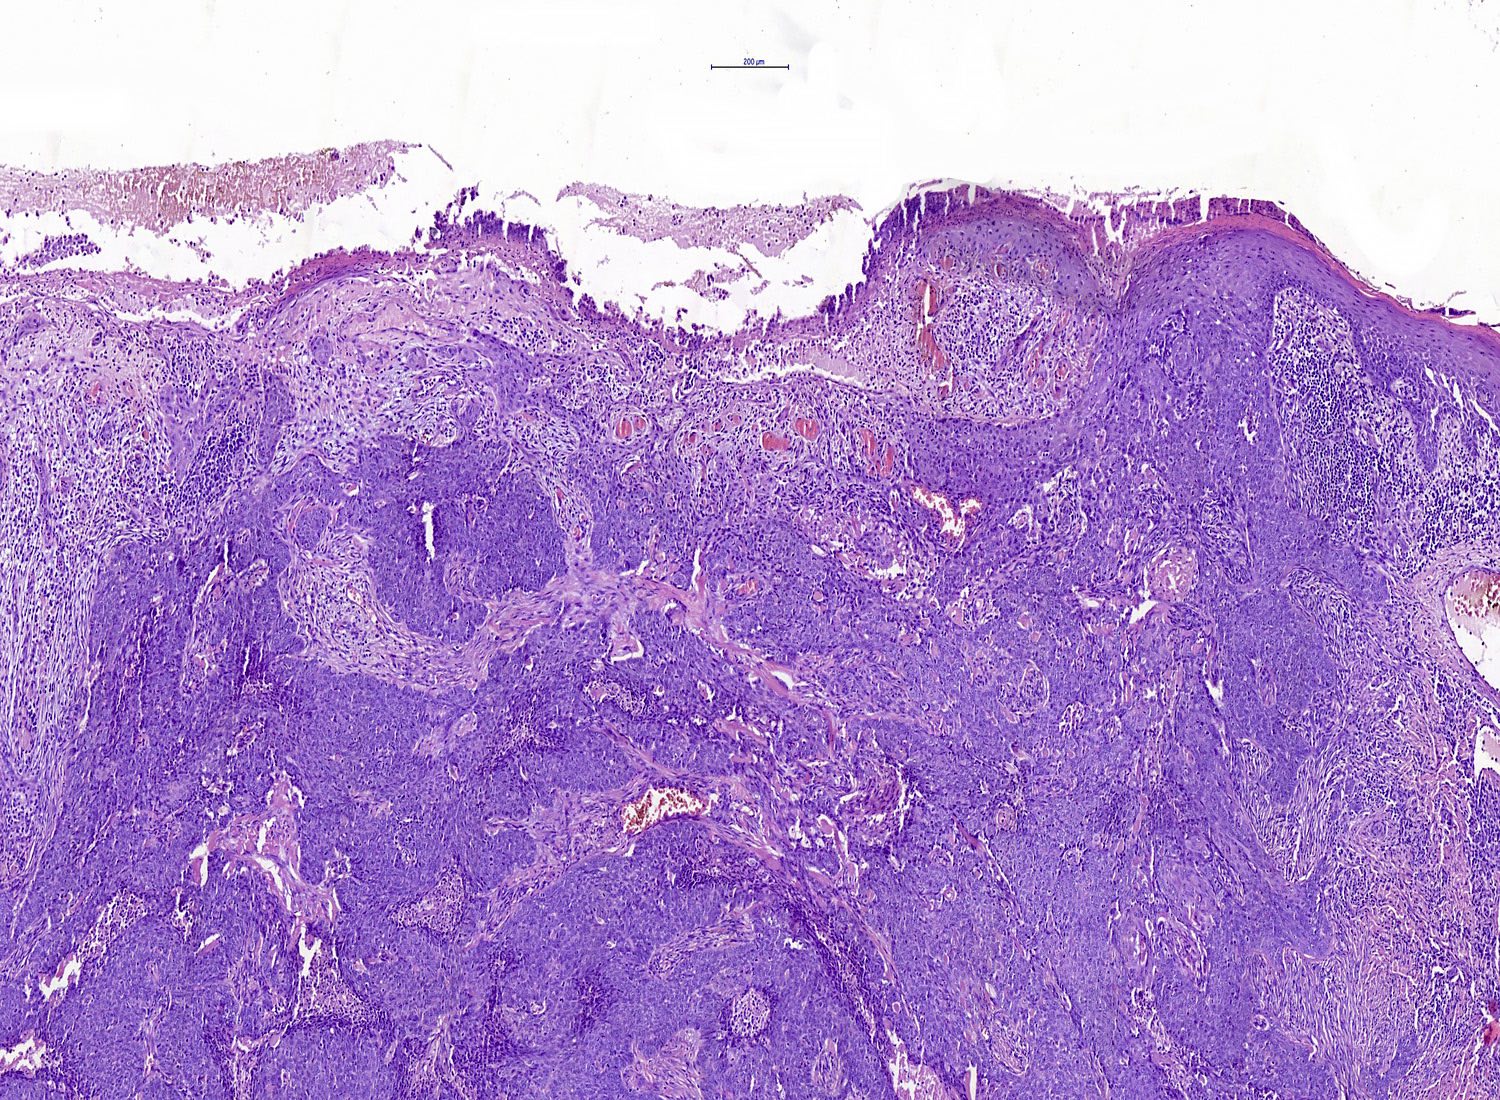

Common variants (Calonje: McKee's Pathology of the Skin, 5th Edition, 2019)

- Nodular and nodulocystic BCC

- Relatively circumscribed mass

- Epidermal or follicular attachment variably present

- Large basaloid lobules with peripheral nuclear palisade

- Lobules may be solid or show central cyst formation due to excessive mucin production

- Fibromyxoid stroma

- Cleft formation between tumor lobules and stroma

- Pleomorphism is generally mild

- Variable mitotic activity and apoptosis

- Sometimes necrosis en masse

Microscopic (histologic) images

Contributed by Antonina Kalmykova, M.D., Phillip H. McKee, M.D., Sate Hamza, M.D., Eduardo Calonje, M.D.,

Wayne Grayson, M.B.Ch.B., Ph.D., James Sampson, M.B.B.S., M.Sc. and Assia Bassarova, M.D., Ph.D.